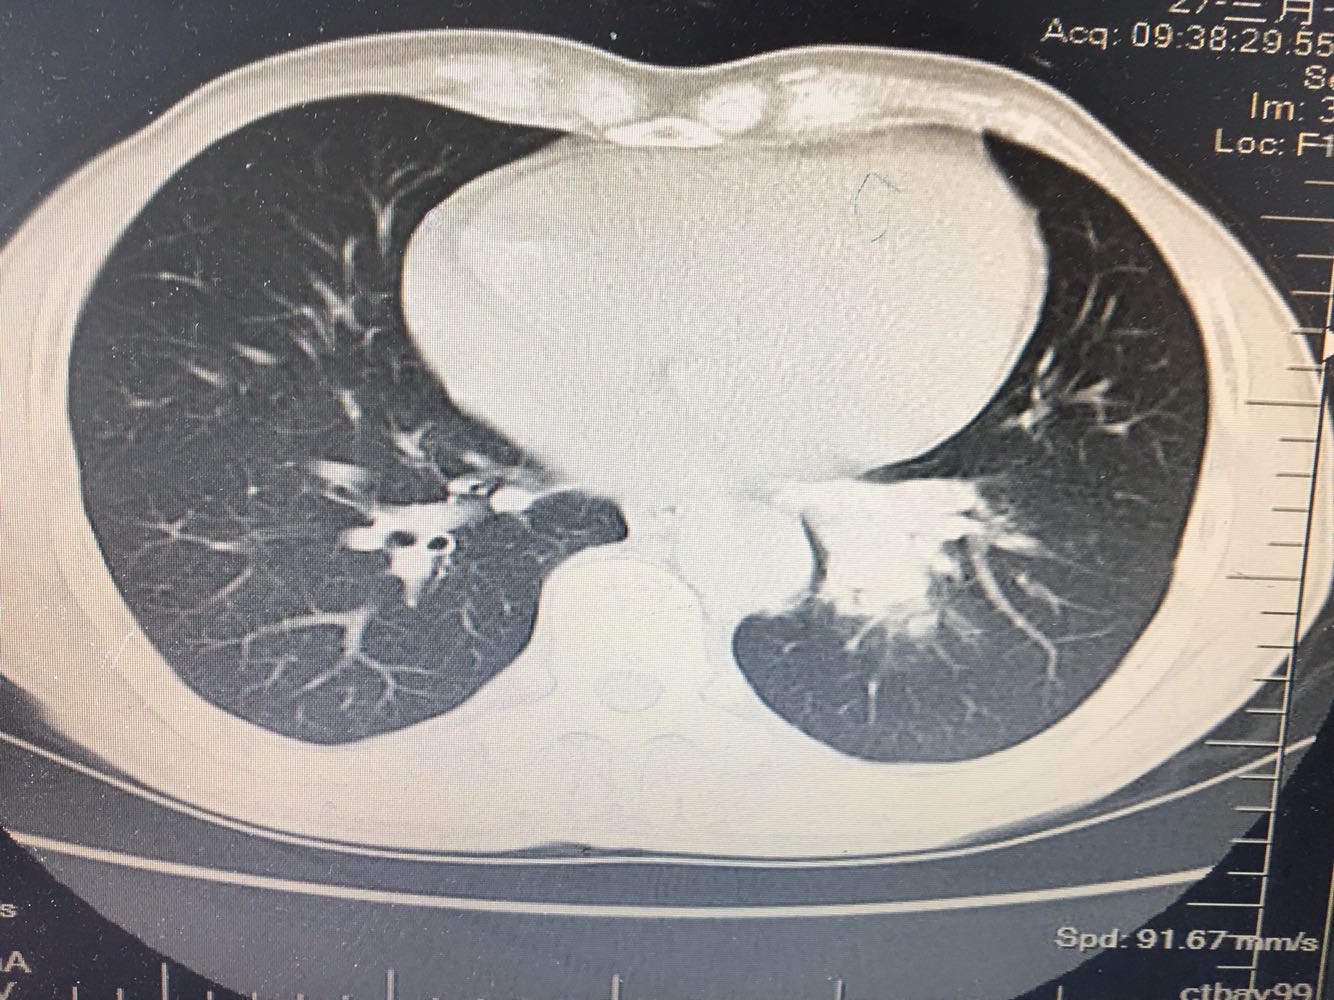

男,63岁,咳嗽1个月入院,患者自述1个月前无诱因咳嗽,阵发性干咳,无痰,时有血丝,无发热,左胸痛,活动后气短,静滴头孢13天无好转,门诊查肺CT后以 肺占位收入我科,病来饮食睡眠可,体重明显下降。既往疝气术后1年,吸烟史30年,每日1包。

左肺癌

左肺中央型肺癌,是否可以手术,还是化疗,放疗,靶向治疗?